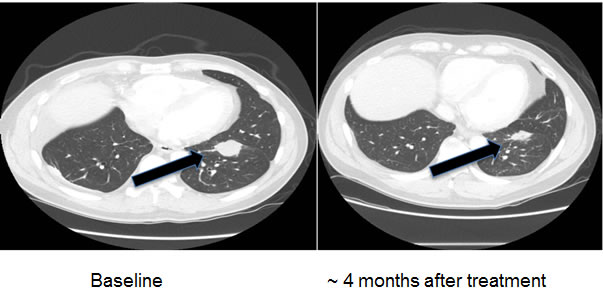

Patients

Three patients with known EGFR-(reversible TKI) resistant mutations (two with insertions in exon 20 (Table 2, Cases 1 and 2) and one with an exon 20 T790M mutation (Case 3) were treated with an EGFR antibody (cetuximab)-based regimen. Both patients with insertions in exon 20 achieved durable partial remissions consistent with the predictions from our structural modeling (Table 2, Figures 7 and 8). The third patient, having the exon 19 (LREA-type) mutation, initially responded to the reversible TKI inhibitor erlotinib (partial remission for 17 months); at the time that the T790M was detected, the patient failed to respond to erlotinib combined with cetuximab, again consistent with the molecular structure predictions.

D770_P772del_insKG in exon 20 |

Partial response, still progression free at 6 months (Figure 8) |

Received cetuximab with chemotherapy and bevacizumab |

Figure 8: Computerized tomographic scan of the lungs of Patient #2 (Table 2) with EGFR exon 20 aberration D770_P772del_insKG before and after treatment with a cetuximab-based regimen shows tumor regression.

Of interest in this regard, we report three patients treated with EGFR antibody cetuximab-based regimens (Table 2). Two of these patients had mutations considered resistant to EGFR TKI inhibitors (D770>GY and D770_P772delsinKG (both in exon 20)), yet attained partial remissions on cetuximab-based therapy (Figures 7 and 8). One patient continues to do well on treatment for over 3.5 years (Table 2, Patient #1, and Figure 7). In contrast, a patient with the exon 20 T790M EGFR-TKI resistant mutation (in addition to the exon 19 sensitive LREAdel aberration) did not respond to the combination of cetuximab and erlotinib (Table 2, Patient #3). Typically, these patients present with the sensitive EGFR LREAdel aberrations and initially respond to reversible TKIs such as erlotinib (and, a salutary effect of erlotinib was indeed seen in our patient early in the disease course), but the resistant T790M mutation then emerges [4]. Similarly Janjigian and colleagues failed to show activity for the erlotinib/cetuximab combination in patients with NSCLC and acquired resistance to erlotinib due to T790M mutations [25]. Our clinical observations are supported by the in silico modeling data (Figures 1 and 5), which demonstrate that exon 20 insertion aberrations would be expected to increase the attractive electrostatic dimerization energies, and such a change could be predicted to predispose to response to an EGFR antibody that attenuates or interferes with dimerization. Further, our modeling suggests that the LREA mutation can react to the combination of cetuximab and erlotinib, but the combination of LREA and T790M mutations can compromise this effect because of resistance of T790M mutant to TKI. Although there are limitations to this study, e.g., the small number of patients and the fact that the responders received combination therapy, the expected rate of response to the other drugs in the combination is low. These data suggest that some patients with gefitinib/erlotinib-resistant EGFR mutations, especially those in the amino acid 770 region of exon 20, may benefit from therapy with EGFR antibodies.